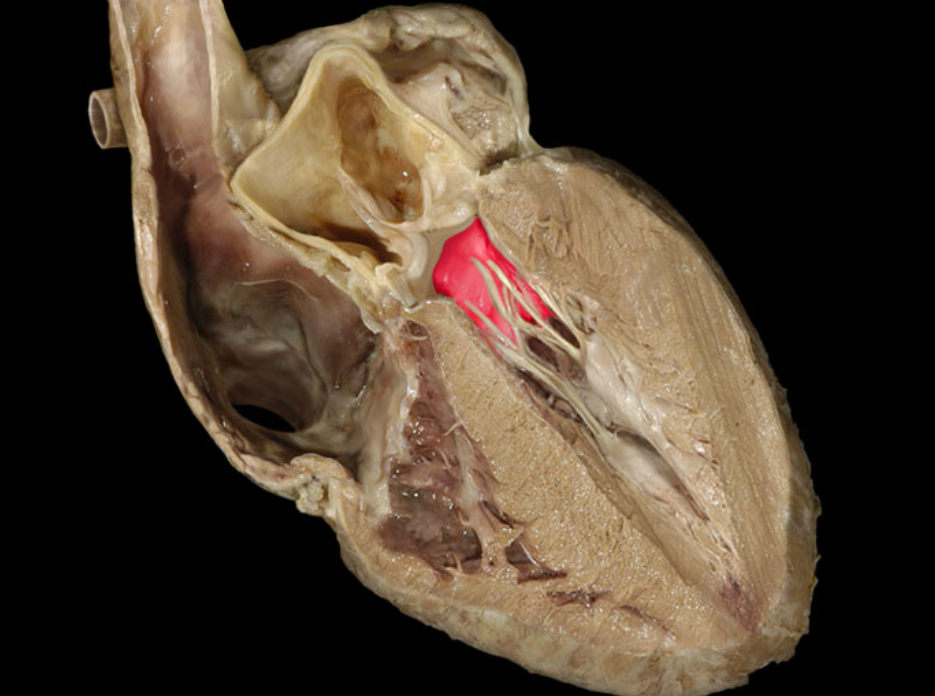

Which of the following best describes the endocardium?

The inner lining of the heart

The left ___ receives blood from the four pulmonary___

atrium, veins

What chamber of the heart pushes blood into the aorta?

left ventricle

The left ventricular contraction forces blood into the____a large artery.

Aorta

Chordae tendineae

Left atrioventricular valve

Left atrium

Left ventricle

Myocardium of left ventricle

Myocardium of right ventricle

Pulmonary valve

Right atrioventricular valve

Right atrium

Right ventricle